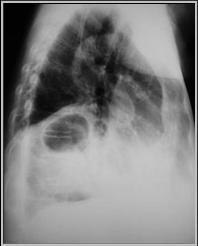

Foramen of Bochdalek Hernia

R3